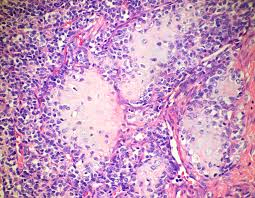

2) 병리학적 소견

• 파괴성 용해성 종양으로, 경계가 불규칙하고 벌레 먹은(moth-eaten) 모양으로 주변 연부 조직으로 확장된다. 골막 반응으로 인해 양파껍질 모양(onion-skin appearance)의 반응성 골 형성이 관찰된다.

• 균일한 작은 원형 세포(small round cells)로 이루어진 병변으로, 세포질이 거의 없거나 풍부한 당원(glycogen)으로 인해 투명해 보인다. 신경외배엽 기원을 나타내는 Homer-Wright rosettes가 존재할 수 있다.

EWSR1 gene(chromosome 22)과 FLI1 gene(chromosome 11) 간의 balanced translocation 인해 EWSR1/FLI1 fusion gene이 생성된다. 해당 단백질은 염색질과 결합하여 전사(transcription)의 조절을 방해해 통제되지 않은 성장과 비정상적 분화를 유도한다.

Ewing sarcoma, Wikimedia Commons